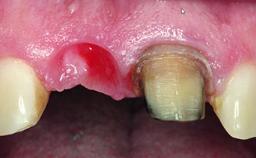

A 32-year-old female Caucasian patient with a compromised maxillary right central incisor was referred to us by a general dentist. Her chief complaints were discomfort and mobility of tooth 11 with unsatisfactory esthetics due to discoloration. The patient reported a previous trauma, some years earlier, as the origin of pathology on the afflicted tooth. Anamnesis was negative for any other dental or periodontal pathology in the remaining dentition. The patient did not take any medication and reported to be a light smoker (5–10 cigs/day). She had high esthetic expectations of her treatment. The extraoral examination revealed a high smile line with full exposure of her maxillary teeth and surrounding soft tissue in the area between the second premolars.

Lip Line No exposure of papillae Exposure of papillae Full exposure of mucosa margin

Esthetic Risk High

Provisional Implant-Supported Prosthesis Prosthodontic margin > 3 mm apical to mucosal margin Prosthodontic margin > 3 mm apical to mucosal margin

Soft Tissue Contour and Volume Slightly compromised